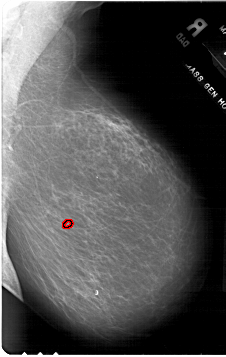

A_1773_1.RIGHT_MLO

RIGHT_CC LINES 5896 PIXELS_PER_LINE 4246 BITS_PER_PIXEL 12 RESOLUTION 43.5 OVERLAY

FILE: A_1773_1.RIGHT_CC.OVERLAY

TOTAL_ABNORMALITIES 1

ABNORMALITY 1

LESION_TYPE CALCIFICATION TYPE PLEOMORPHIC DISTRIBUTION CLUSTERED

ASSESSMENT 4

SUBTLETY 2

PATHOLOGY BENIGN

TOTAL_OUTLINES 1

BOUNDARY